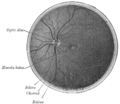

| Diagram of the blood vessels of the eye, as seen in a horizontal section. (Central retinal vein not labeled, but region is visible. The central retinal vein is at bottom running away from the retina through the optic nerve.) | |

الوريد الشبكي المركزي (الوريد الشبكي) هو وريد قصير يمر عبر العصب البصري ، ويترك العصب البصري 10 مم من مقلة العين ويصرف الدم من الشعيرات الدموية للشبكية إلى الوريد العيني العلوي أو إلى الجيب الكهفي مباشرة. يختلف تشريح أوردة مدار العين بين الأفراد ، وفي بعض الحالات يصب الوريد الشبكي المركزي في الوريد العيني العلوي ، وفي بعض الحالات يصب مباشرة في الجيب الكهفي..[1][2]